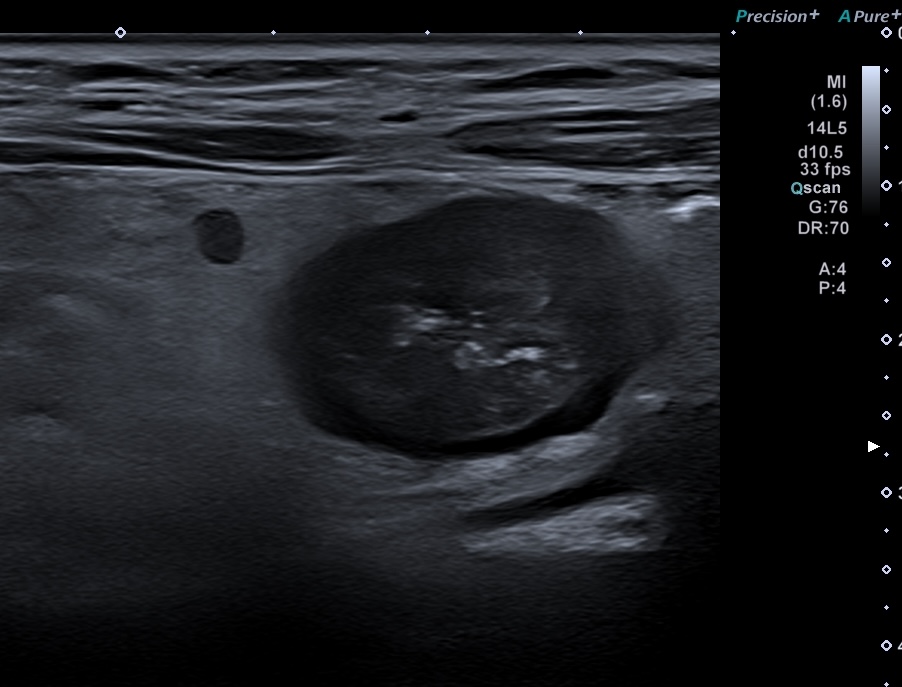

Epaisseur > 3 mm

Doppler +

Graisse inflammée

Ganglions inflammatoires (> 6 mm de petit axe)

En cas d'inflammation, on peut voir 4 types de modifications échographique: